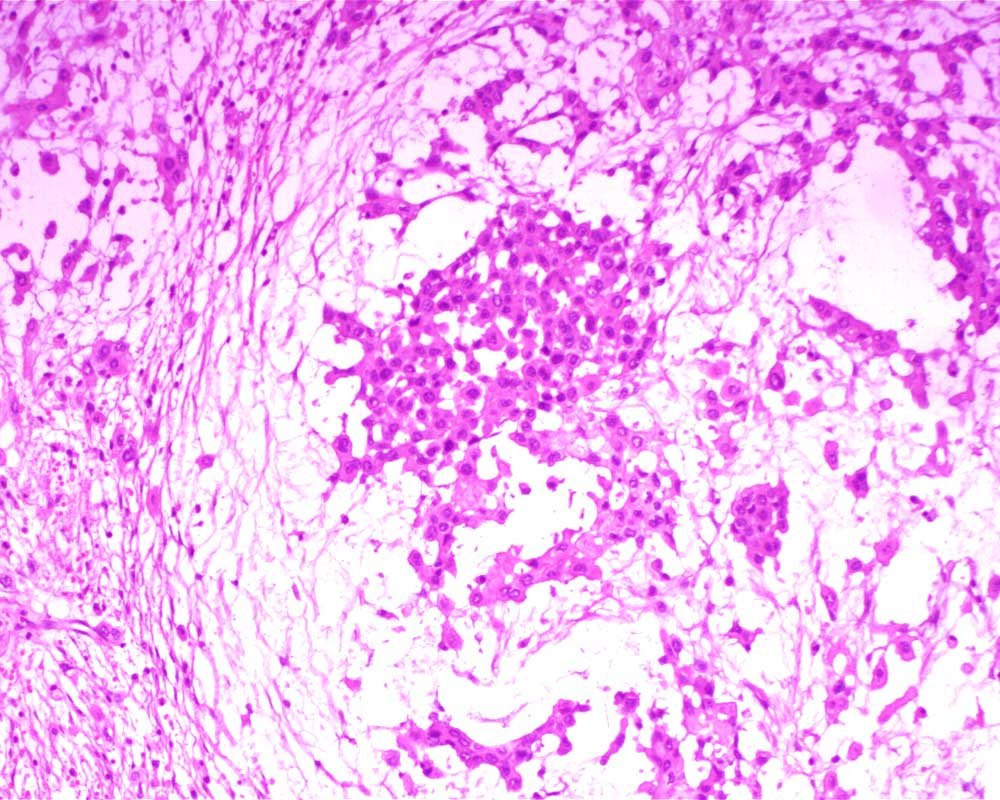

Case: PeritonealLesion

Final Diagnosis: